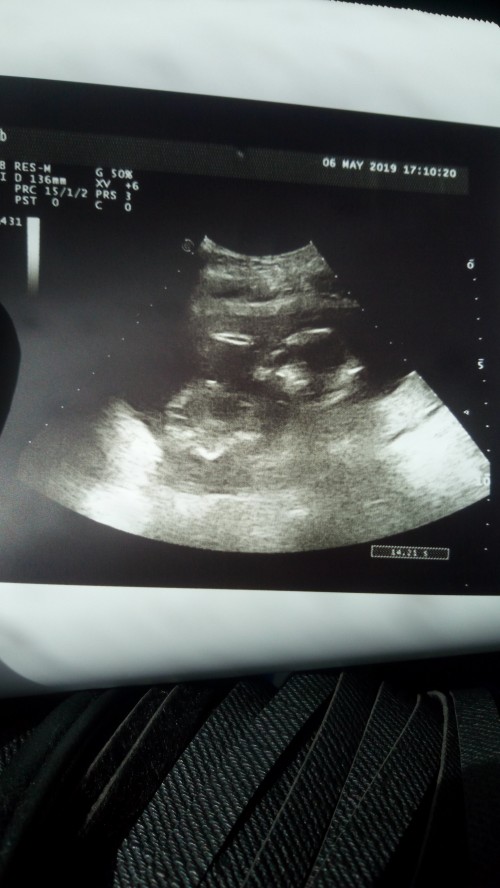

Kizlar bebegim 16 hafta 4 gunluk ama ultrasonda 17 haftalik gozuktu ve fotosunu istedim doktordan agzi avikmi bebisimin esniyomu tam anlamadim anlayan bakabilirmi :)

Işık ve sudan dolayı öyle de çıkmış olabilir ama artk ağzını da açıp kapatıyor. Benim bebegim bize dil bile çıkarmıştı izlerken. Fotoğraf olarak yakalayamamistik bir türlü